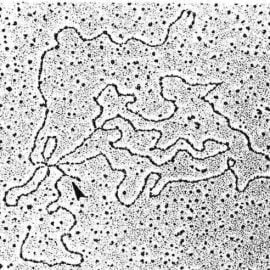

Sama ospa wietrzna nie jest groźną chorobą, mimo iż należy do chorób zakaźnych, jakie wywołują panikę. Często rodzice maluchów chorujących na wiatrówkę demonizują ja. Owszem objawami ospy są wypryski, krosty na całym ciele, które swędzą. Najbardziej dokuczliwym objawem ospy jest świąd, w wyniku którego strupy po krostach są zrywane i powodują blizny na skórze. Niestety ospa lubi wywoływać powikłania i to właśnie one są niebezpieczne.